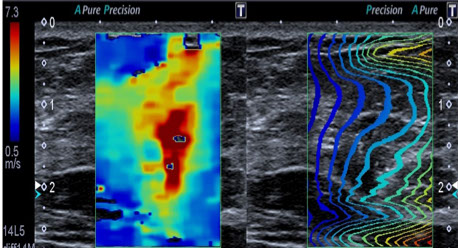

Ultraschall

- Brustultraschall inklusive Elastographie

- Schwangerschaft, inklusive Farbdoppler und 3D Babyfernsehen